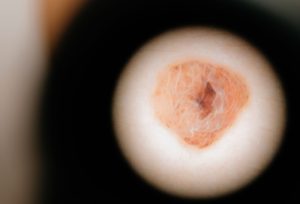

Lesões vasculares da pele: o que são, diagnóstico e como tratar

Lesões nos vasos sanguíneos são quase sempre benignas e podem ser tratadas com tecnologias a laserAs lesões vasculares da...